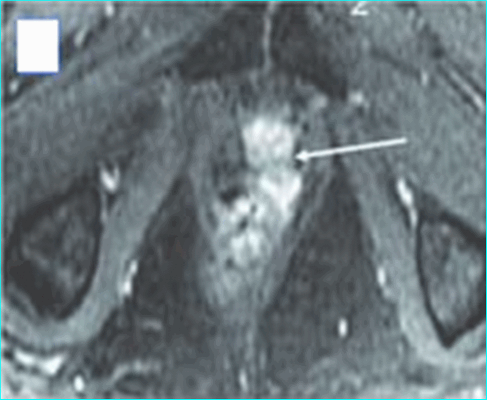

Пациент К., 1965 года рождения, при плановом обследовании в поликлинике по месту жительства в марте 2017 г. выявлено повышение уровня ПСА до 6,5 нг/мл, в связи с чем в ГКБ № 29 Москвы выполнена трансректальная биопсия предстательной железы, гистологически верифицирована ацинарная аденокарцинома 6 (3+3) баллов по Глисону. Больной самостоятельно обратился в МНИОИ им. П.А. Герцена. При пересмотре стекол препаратов биопсии предстательной железы в условиях патоморфологического отделения МНИОИ им. П.А. Герцена на фоне гиперплазии предстательной железы с очагами атрофии в 5 фрагментах из 12 выявлен рост ацинарной аденокарциномы 7 (4+3) баллов по Глисону, занимающей до 100% площади столбиков. По данным УЗИ и МРТ малого таза, предстательная железа размером 42×34×30 мм, объемом до 30 см 3 (рис. 3). Рис. 3. Магнитно-резонансная томограмма малого таза.

В периферической зоне правой доли определяется очаг раннего накопления контрастного препарата 13×10 мм без инвазии в капсулу железы и семенные пузырьки. В полости малого таза измененные лимфатические узлы не выявлены. При пальцевом ректальном исследовании предстательная железа не увеличена в размере, не деформирована, эластической консистенции, без пальпируемых узловых образований, междолевая бороздка сглажена. Слизистая оболочка прямой кишки над железой подвижна. Другой очаговой опухолевой патологии при комплексном обследовании не выявлено. На основании обследования установлен клинический диагноз: рак предстательной железы I стадии сТ2аN0M0. Больной обсужден на консилиуме с участием хирурга, химиотерапевта, лучевого терапевта и онколога: учитывая размер, локализацию и распространенность опухолевого процесса, отсутствие отдаленных и регионарных метастазов, рекомендовано хирургическое лечение. 10.04.17 больному выполнено хирургическое лечение в объеме радикальной простатэктомии, расширенной тазовой лимаденэктомии. Послеоперационный период протекал гладко, без особенностей. При контрольном УЗИ органов малого таза и вен нижних конечностей от 17.04.17 в полости малого таза объемных образований не выявлено. Поверхностные и глубокие вены обеих конечностей проходимы, без тромбоза и флебита. По данным цистографии от 17.04.17, подтверждена герметичность везикоуретрального анастомоза, в связи с чем 19.04.17 уретральный катетер удален, восстановлено самостоятельное мочеиспускание. Проведены антибактериальная, инфузионная, симптоматическая терапия и профилактика тромбоэмболических осложнений с положительным эффектом. Послеоперационная рана зажила первичным натяжением.